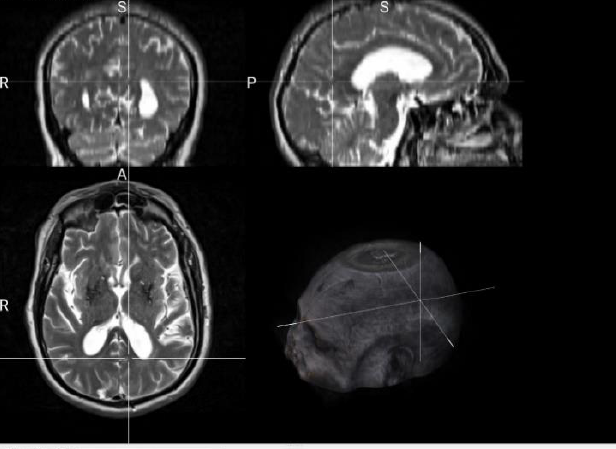

The PPMI dataset contains MRI images of patients in DICOM (Digital Imaging and Communications in Medicine) format files [50], which represents a two-dimensional image of a single angle of the person; therefore, the first step of the pre-processing was the reconstruction in a three-dimensional format, or in NIfTI (Neuroimaging Informatics Technology Initiative) [74], a format notoriously used in the medical field. Fig 4(a) shows the original DICOM format of an MRI belonging to PPMI visualized by using the tool “MicroDicom” [36], while Fig. 5(b) shows the three-dimensional NIfTI format if the same image produced by the “MRIcroGL”[70] tool.

Refer to caption

Figure 5: MRIcroGL interface